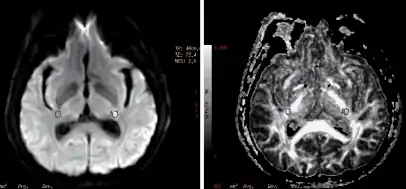

a)Diffusion weighted imaging b) and fractional anisotrophy measurement in individual with transient ischemic attack

According to guidelines from the American Heart Association and American Stroke Association Stroke Council, patients with TIA should have head imaging "within 24 hours of symptom onset, preferably with magnetic resonance imaging, including diffusion sequences".[4] MRI is a better imaging modality for TIA than computed tomography (CT), as it is better able to pick up both new and old ischemic lesions than CT. CT, however, is more widely available and can be used particularly to rule out intracranial hemorrhage.[12] Diffusion sequences can help further localize the area of ischemia and can serve as prognostic indicators.[16] Presence of ischemic lesions on diffusion weighted imaging has been correlated with a higher risk of stroke after a TIA.[17]